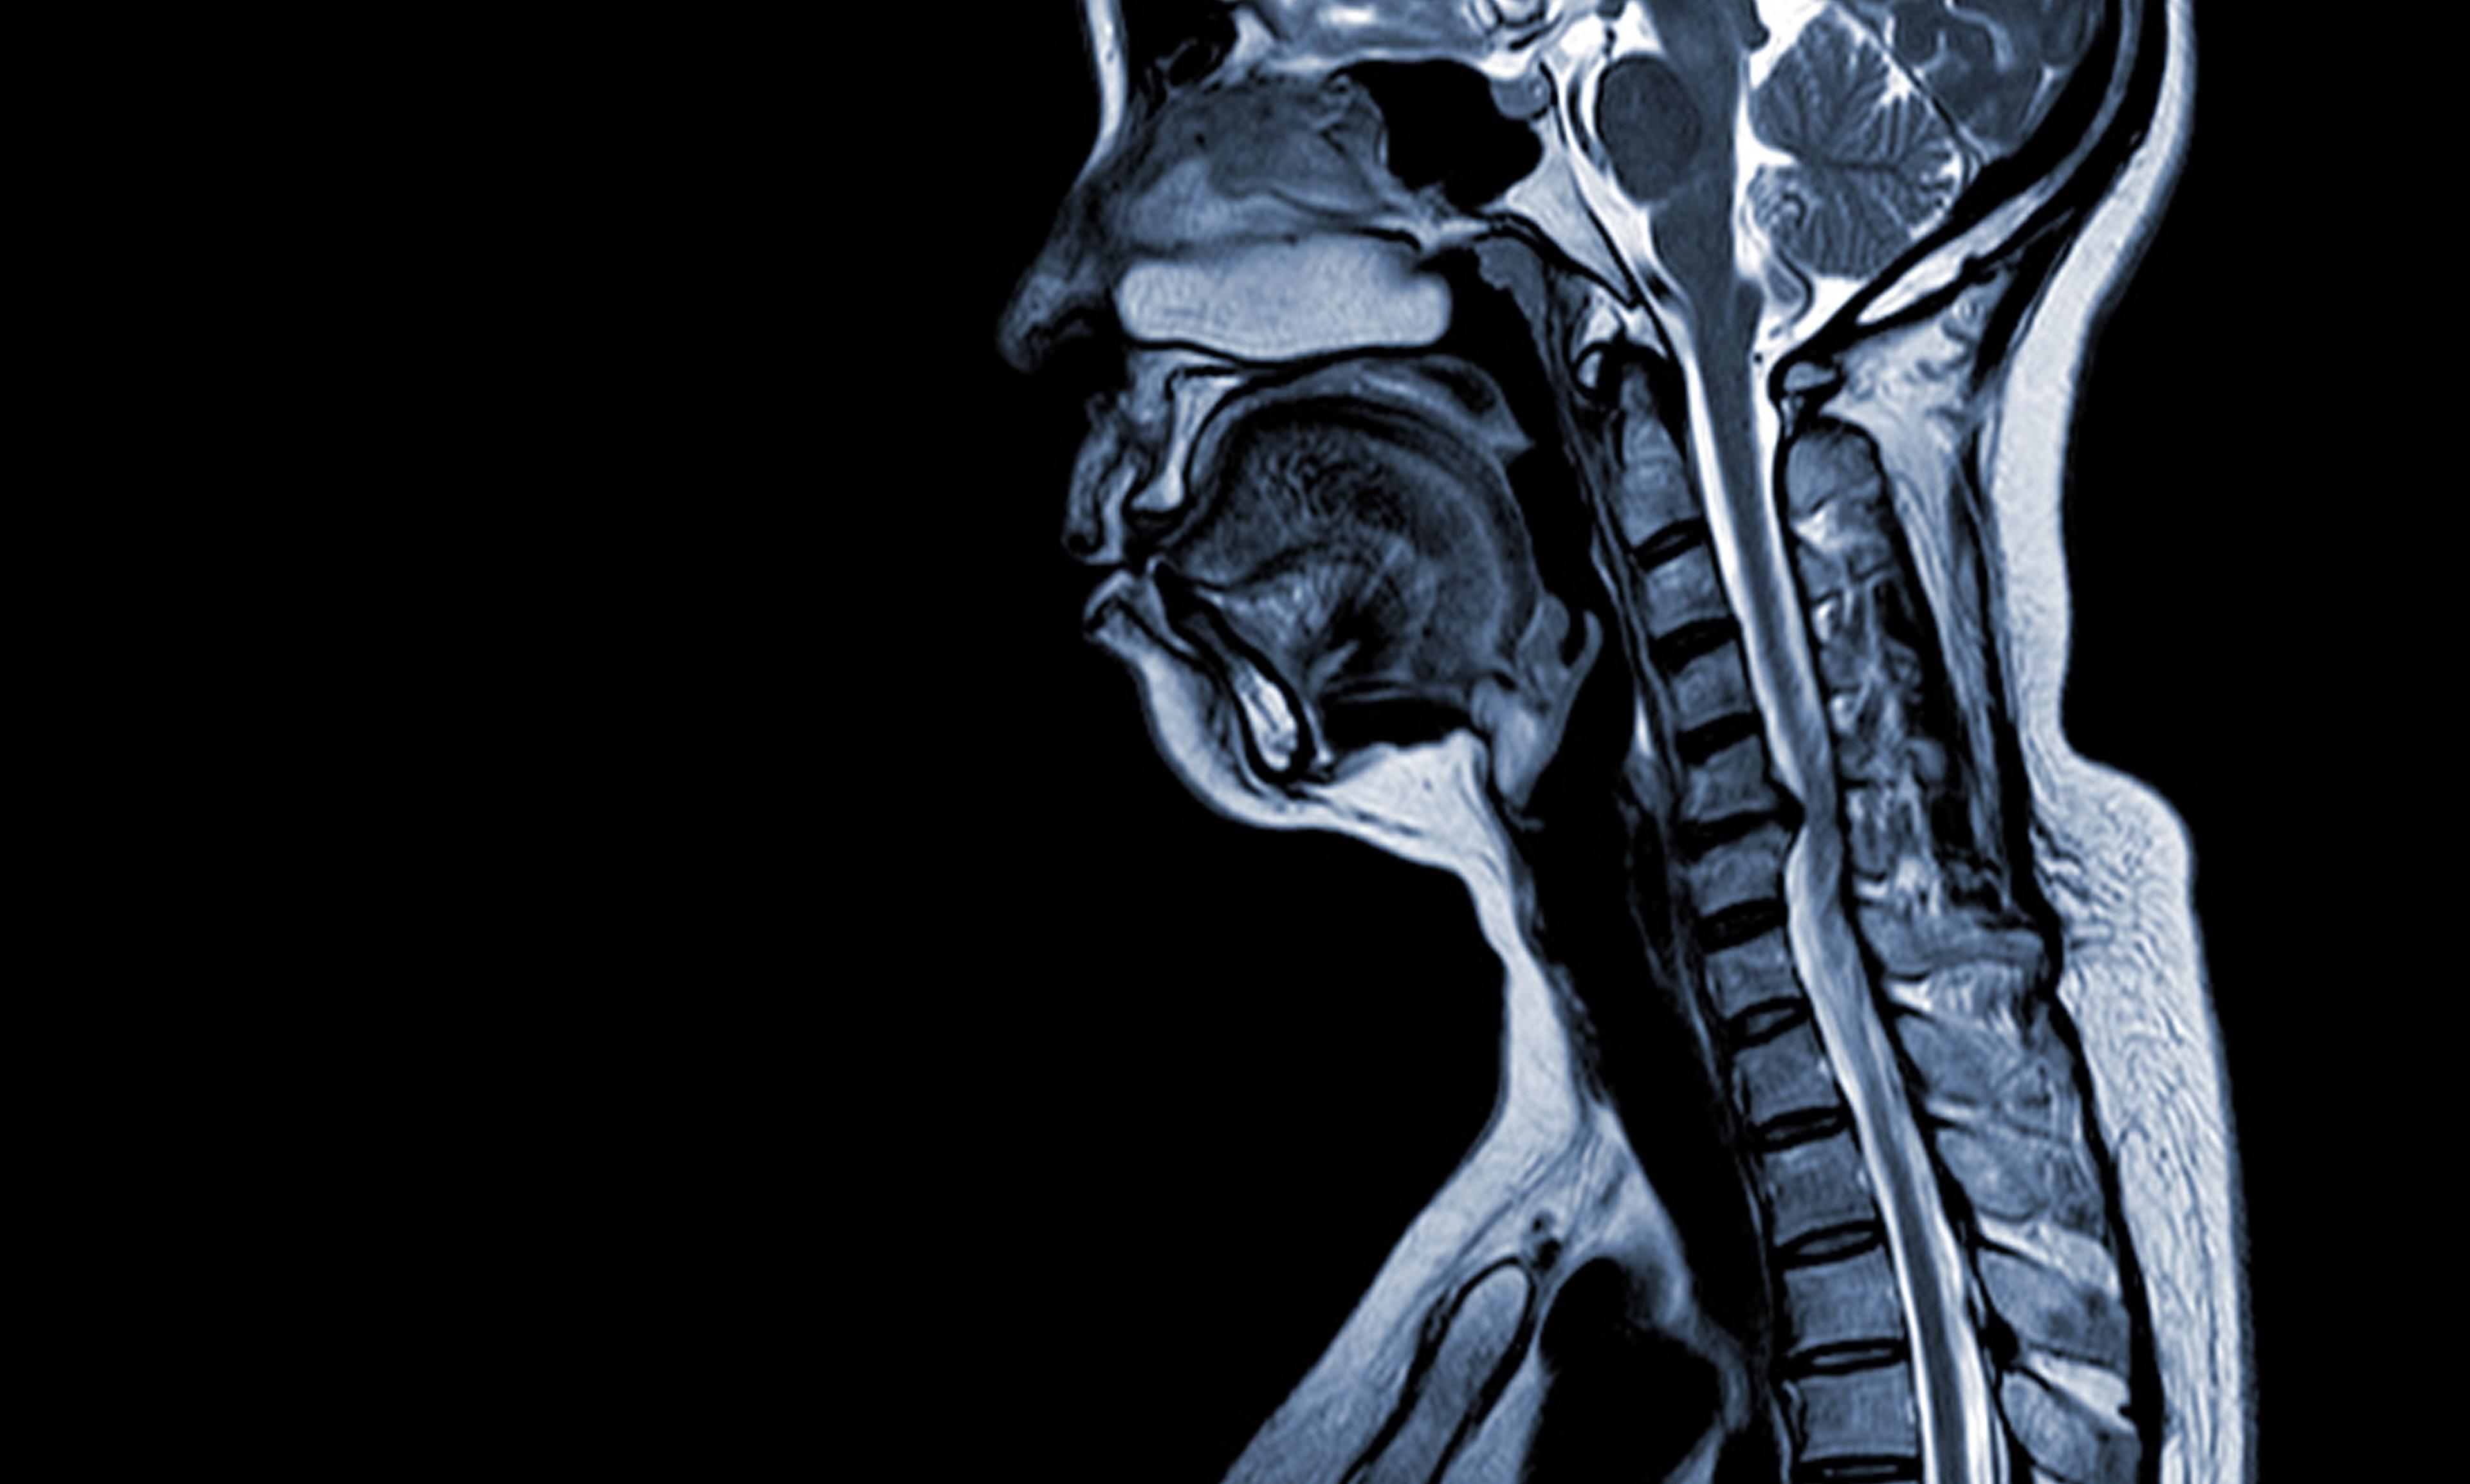

C4-C5 Disc Herniation